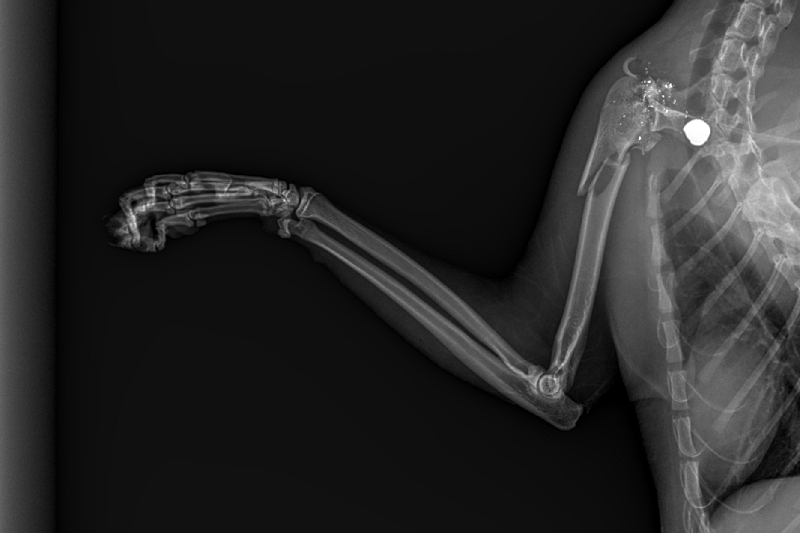

The bullet broke his arm and is currently lodged inside his body with many fragments scattered throughout his shoulder. I could go on about the vile nature of his attacker, but this isn't about him/her. It's about Jonesy.

From his initial consultation, it appears as if Jonesy might need two separate procedures. The first is to get the bullet and the fragments out of his body. The second is to either repair his leg or amputated it all together.

In this post I will add pictures of him and his x-rays. All funds received will be used for his medical procedure(s) and post Op care/visits.